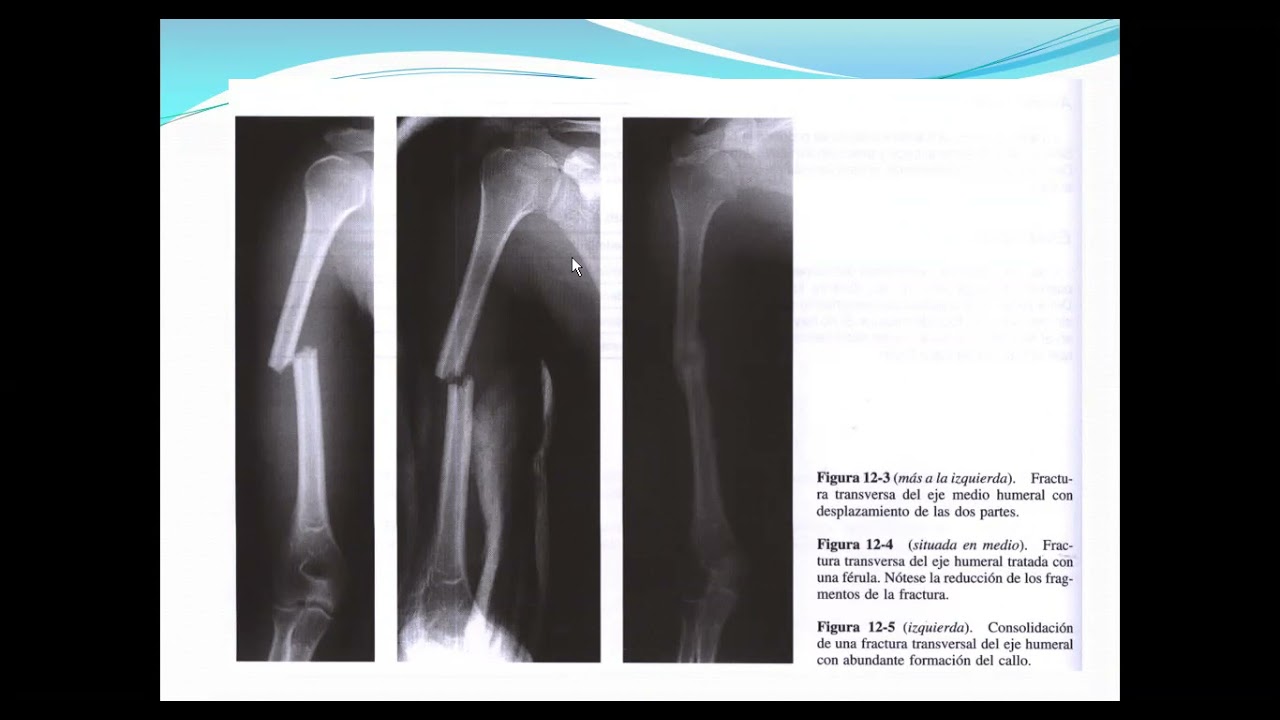

zoom fx de la diafisis de humero

Fracturas del húmero distal